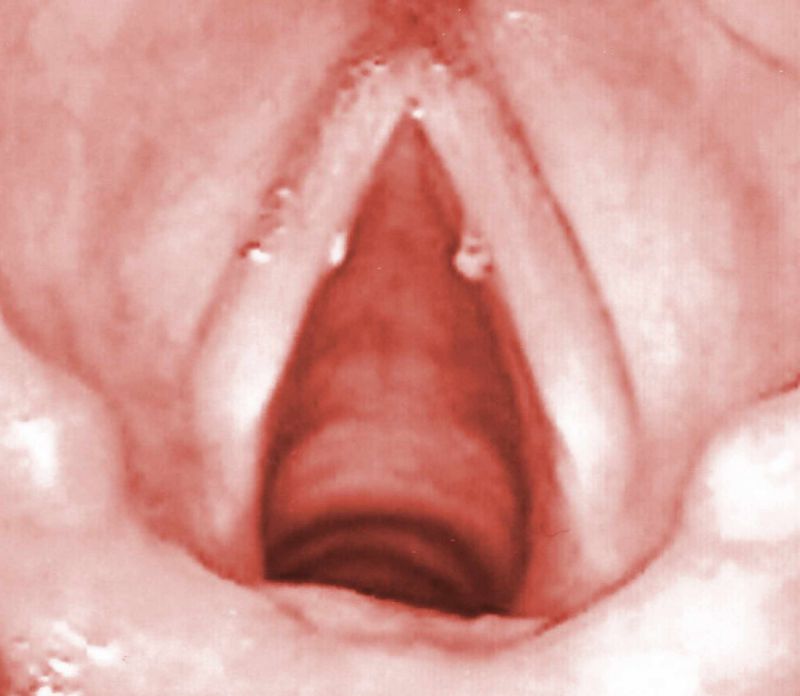

Die berüchtigten Stimmlippenknötchen. Sie entstehen durch eine nachhaltig ungesunde Tonerzeugung. Nicht selten das vorzeitige Karriereende für angehende Heavy-Metal Sänger/innen.

Sind die Knötchen einmal verhärtet, so lassen sie sich nur noch operativ entfernen.

Selbst bei angemessener Erholung konditioniert sich die Motorik der tonerzeugenden Muskulatur entsprechend der immer wiederkehrenden Überbeanspruchung. Diese Fehlfunktion führt im Laufe der Zeit zu Entzündungen der Stimmmuskulatur und schließlich zu den berüchtigten Stimmlippenknötchen.

Stimmlippenknötchen